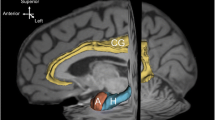

We extended the current literature with our examination of former high school football players who had at least two mild TBIs related to their high school football experiences. However, these former athletes have not received a concussion since that time, a period of at least fifteen years. We compared the concussed group to a matched group of control participants who also played high school football but do not have a history of concussive injuries. We also examined how these injuries may be related to worse cognitive performance. We used high-resolution FSPGR MRI scans from a 3-Tesla imaging system to elucidate volumetric differences between the past-concussed group and the control group with a priori hypotheses that the past-concussion group would have less total brain volume (i.e. intracranial volume, ICV), total white matter volume, total gray matter volume, hippocampal volume, anterior cingulate volume, and lateral ventricular volume compared to the control group. Further, we explored two brain-behavior correlations: the relationship between hippocampal volume with memory functioning based on previous studies implicating medial temporal lobe structures are related to delayed recall (Tremblay et al. 2013), as well as between gray matter volume and overall cognitive functioning based on previous aging literature showing this broad relationship (Kramer et al. 2007).

The Repeatable Battery for the Assessment of Neuropsychological Status (RBANS) was used to assess cognitive functioning (Randolph et al. 1998). A total of 12 subtests are used to generate 5 index scores (i.e., Visuospatial/Constructional, Attention, Language, Immediate Memory, and Delayed Memory) and one Overall Scaled Score for the whole test. Raw scores are converted to standard scores (i.e., mean = 100, standard deviation = 15) based on age (Fig. 1).

An automated measure of total intracranial volume (ICV) was also used in conjunction with the Freesurfer package (Buckner et al. 2004). Extracting ICV using this method has also been shown to be comparable to manual tracing. This volume served as both a dependent measure as well as a way to correct ROIs for overall head size. Total gray matter volume and white matter volume were extracted directly from the Freesurfer output. The anterior cingulate cortex comprised the volumes labeled the caudal anterior cingulate and rostral anterior cingulate. Our hypotheses were not hemisphere specific, so the left and right volumes for the hippocampus, lateral ventricles, and anterior cingulate (i.e., caudal + rostral) were summed to represent their respective bilateral structures. To control for ROIs, the slope (b) of the ROI volume was regressed onto the ICV. That variable was entered into the following equation to normalize each ROI for head size:

Independent t-test analysis comparing whole brain volume between the concussed and the control groups was not significant [t(38) = 0.029, p = .98] (Table 2). The average ICV for the sample was 1,405,323 mm3, which was used to calculate the normalized volumes for each of the ROIs. There were no statistically significant differences in volumes between the two groups when comparing overall gray matter volume [t(38) = 0.451, p = .65], overall white matter volume [t(38) = 0.432, p = .66], bilateral lateral ventricles [t(38) = −0.538, p = .59], bilateral anterior cingulate volume [t(38) = 0.509, p = .61], or bilateral hippocampal volume [t(38) = 0.033, p = .74]. Given the potential influence of other variables, we employed an analysis of covariance (ANCOVA) to ensure that age did not affect the relationship between group status and volumes. Covarying for age, ANCOVAs did not reveal any statistically significant group differences (all p-values > .05).

Results of our study suggest a lack of volume differences in the brains of middle-aged men who experienced multiple mTBIs compared to those without mTBIs in the context of their high school football careers. This lack of volumetric differences was seen in both overall intracranial volume as well as in specific regions that have previously been associated with smaller volumes such as overall gray matter, white matter, lateral ventricles, the anterior cingulate, and the hippocampus.